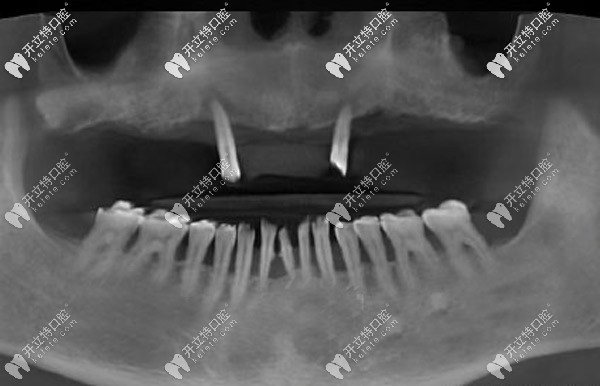

經(jīng)過(guò)口腔CT三維拍片確診,周老先生患有牙周炎,且有牙齦萎縮的情況。羅緣口腔的種植醫(yī)生通過(guò)數(shù)字化動(dòng)態(tài)導(dǎo)航系統(tǒng)在計(jì)算機(jī)上重建口腔頜骨三維立體模型。

與周老先生進(jìn)行溝通后,確定了種植體嵌入位置、數(shù)量、種植深度、植體傾斜角度等等,并采用上頜6顆即刻種植技術(shù),運(yùn)用“數(shù)字化動(dòng)態(tài)導(dǎo)航種植”方案。